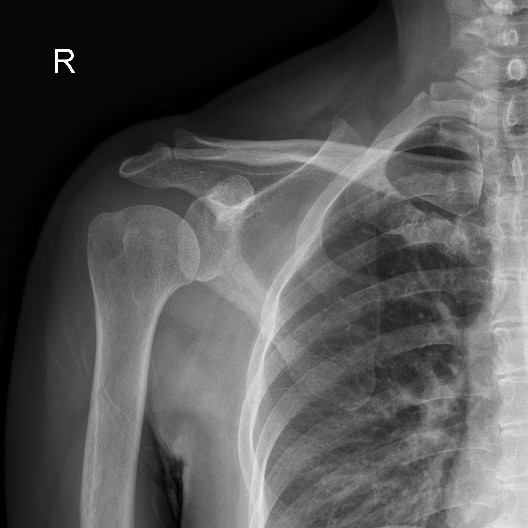

术后X光片显示钙化灶已消失